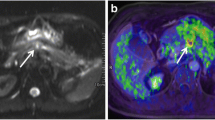

Images of a 56-year-old man with pancreatic head cancer (arrow) (T4N1M1). (a) Pre-contrast T1-weighted MR (b) PET (c) fused PET/venous phase CE T1-weighted VIBE MR. (d–f) DCE-MRI color maps: (d) IAUC 60 (e) peak (f) Ktrans (g) diffusion-weighted image (b = 1000) (h) ADC map (i) MR spectroscopy. This patient underwent chemotherapy and overall survival was 199 days

Images of a 76-year-old man with pancreatic head cancer (arrow) (T1N1M0). (a) Venous phase CE T1-weighted MR (b) axial PET (c) fused PET/venous phase CE T1-weighted MR. (d–f) DCE-MRI color maps: (d) IAUC 60 (e) peak (f) Ktrans (g) diffusion-weighted image (b = 1000) (h) coronal PET (i) MR cholangiopancreatography shows marked dilatation of common bile duct and main pancreatic duct. This patient underwent Whipple operation and overall survival was 638 days